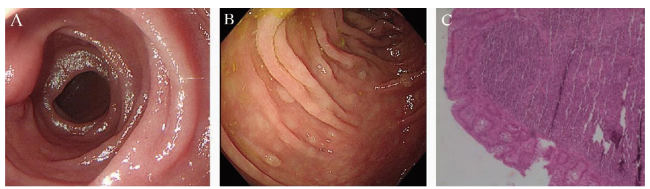

病例1 患者女,49岁,2019年6月20日于本院常规体检,主诉无明显不适,体格检查无殊。否认高血压、糖尿病等其他病史。血常规、血生化、肿瘤标志物等实验室检查均未见明显异常。腹部CT平扫示胃窦部胃壁稍增厚,肝囊肿,胰头部脂肪浸润。B超未见体表及腹腔深部淋巴结肿大。结肠镜示结肠黏膜未见异常。胃镜示十二指肠降段黏膜散在息肉样增生,表面粗糙,色灰白,病变分布于十二指肠乳头周围,占肠腔周径1/2~2/3(图1A);病灶黏膜病理:十二指肠乳头周围淋巴组织增生,黏膜内多个淋巴滤泡结构(图1B)。免疫组化:肿瘤细胞CD20(+),CD10(+),Bcl-2(+),Bcl-6(+),CD3(-),CD5(-),Ki-67(+,5%~10%),CD21 FDC(+)。结合HE染色及免疫表型诊断为D-FL(1级)。患者因无任何临床症状拒绝治疗,鉴于D-FL属于惰性淋巴瘤,预后较好,建议患者定期胃镜检查观察。2021年4月外院复查胃镜示十二指肠降部乳头处黏膜粗糙(图1C),该处组织病理为十二指肠降部黏膜慢性炎伴息肉状增生。确诊D-FL 4年,电话随访至截稿日患者主诉无不适感,虽未采取相关治疗,但疾病无进展迹象。

图1 病例1 D-FL患者胃镜及病理图片

注:A为2019年6月胃镜下十二指肠降段黏膜表现;B 为2021年4月胃镜下十二指肠降段黏膜表现;C为十二指肠降段黏膜病理结果(HE染色,40)。